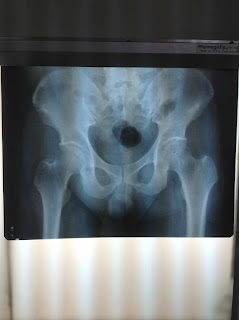

Orthopedics- One of the surgical rotations I've enjoyed because of its mechanical and physical aspect.

Patient on leg traction